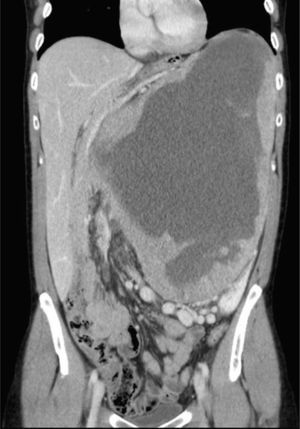

A 46-year-old patient with no medical history of interest came to our consultation complaining of postprandial fullness and a mass in the epigastrium (Fig. 1). Abdominal CT showed a large mass measuring 37cm×27cm×30cm situated between the left lobe of the liver, pancreas, kidney and splenic hilum (Fig. 2). There was a slight elevation in tumor markers: Ca 19.9 (80.8U/ml), and Ca 15.3 (85U/ml). We performed an en bloc resection of the mass, and the pathology study reported an eosinophilic variant of chromophobe cell carcinoma (Fuhrman nuclear grade 3) with extensive central necrosis (Fig. 3). This type of tumor is uncommon. The prognosis is good, with little tendency toward advancing or metastasizing, and with a 10-year survival rate of approximately 90%. The most important prognostic factors are tumor size, presence of sarcomatoid differentiation and tumor necrosis.